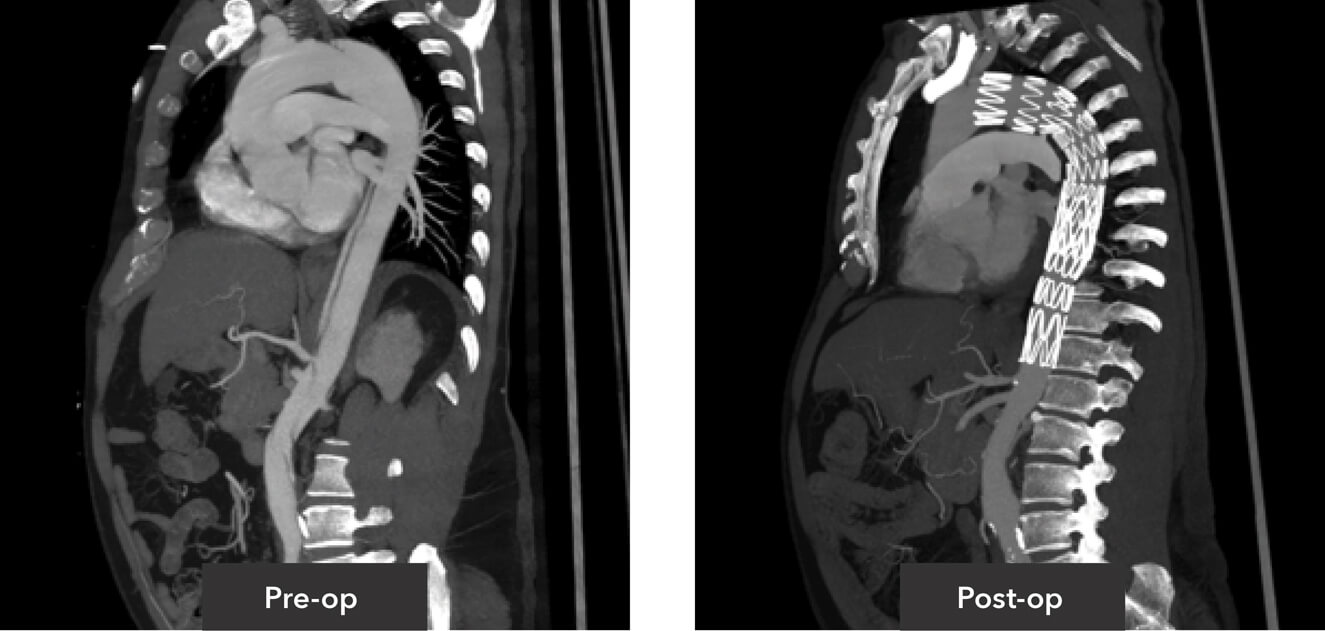

Sagittal view pre-op/post-op CT imaging